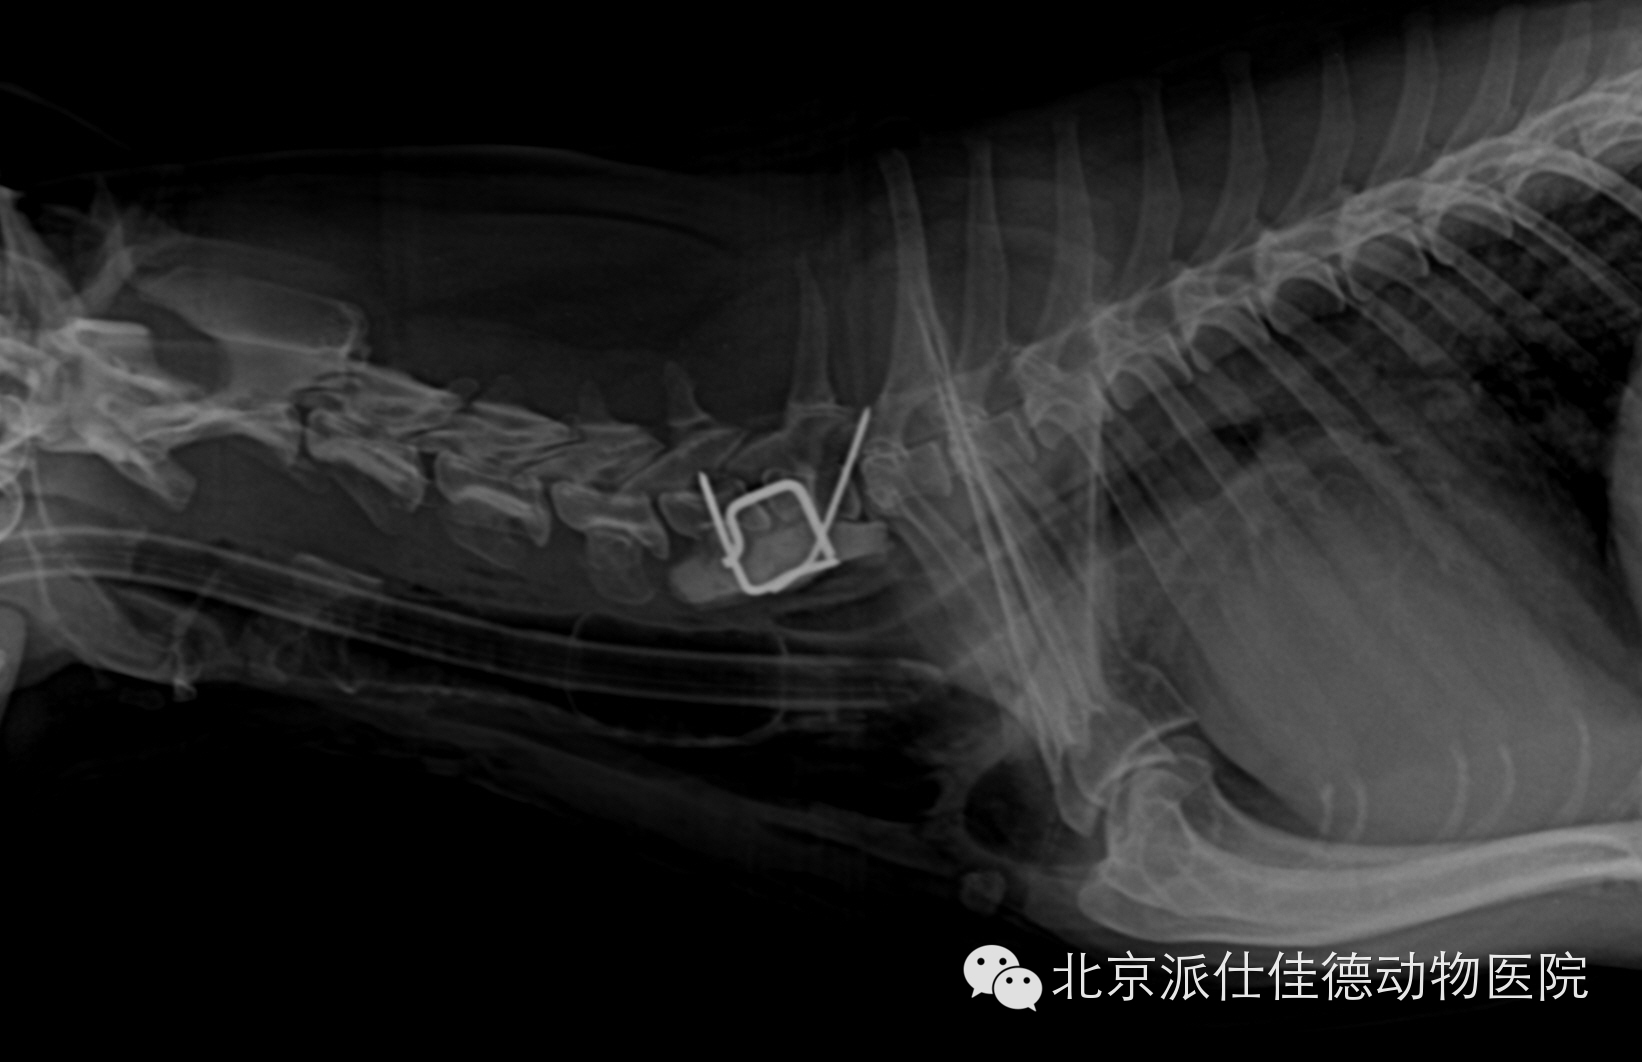

7.有些动物表现腰疼,一直按椎间盘突出治疗,结果经诊断为脊椎肿瘤或是椎管内肿瘤或是脊髓本身肿瘤引发。